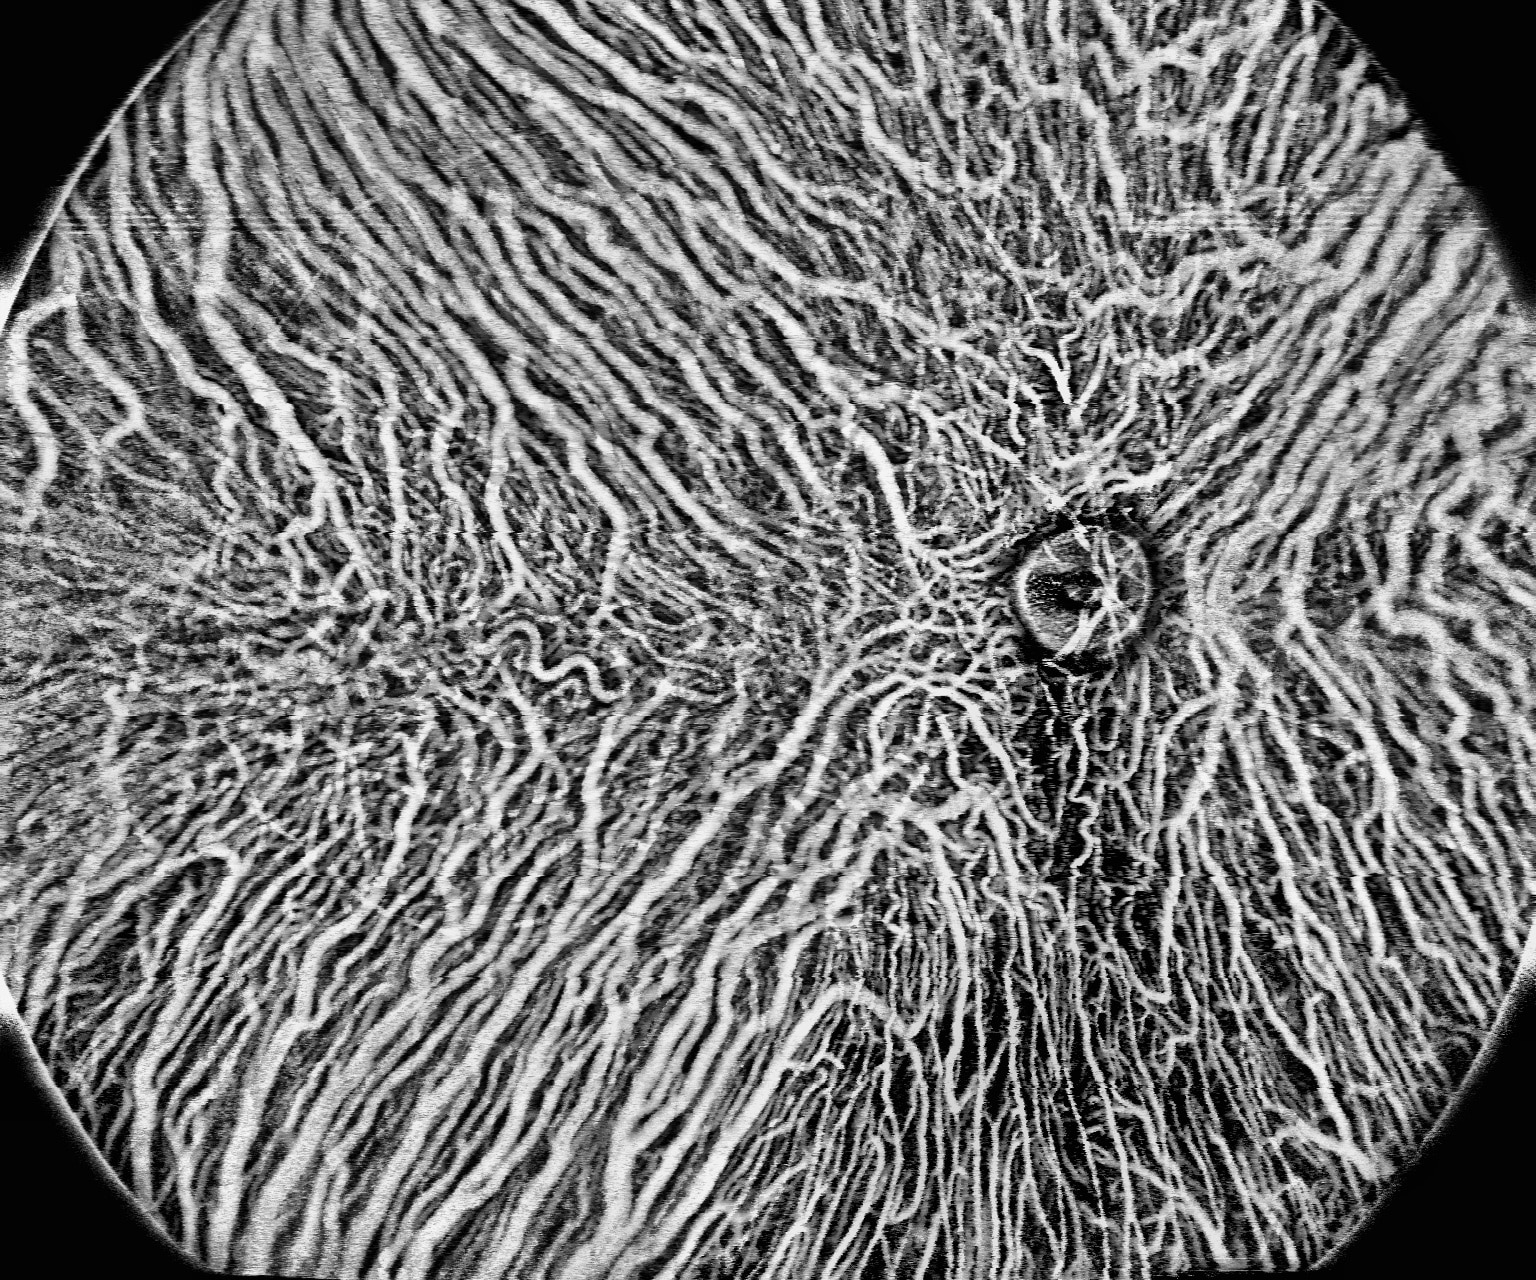

400kHz speed full-range swept-source OCT for anterior and posterior

- Full-Range wide-field Swept Source OCT

- Wide-field OCTA

- Choroid OCTA with Quantification Parameters

- HD Anterior Scan with Anterior OCTA